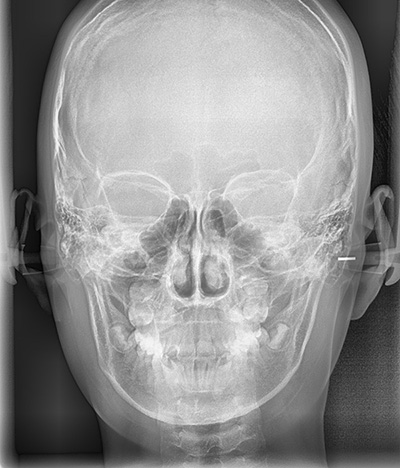

옆얼굴 뿐만 아니라 정면 얼굴 엑스레이와 어린이들의 경우 현재 성장단계는 어떠한지 알기 위하여 손사진도 같이 촬영합니다. CT 촬영이 필요한 경우에는 추가로 CT 촬영도 하게 되지요.

성장단계 검사